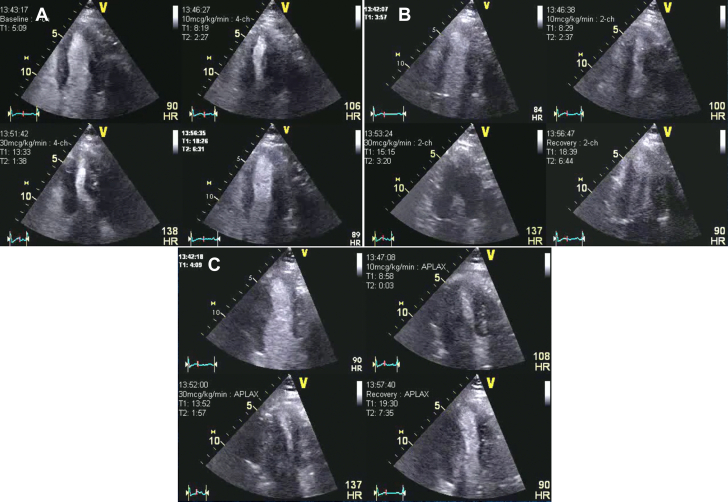

Figure 4.

Patient 1 Follow-Up: Dobutamine Stress Echocardiography

Dobutamine stress echocardiography with an ultrasound enhancing agent, end-systolic frames at different views and stages. (A) Apical 4-chamber view. (B) Apical 2-chamber view. (C) Apical 3-chamber view. The quad images represent the resting, low-dose, peak stress, and recovery stages of the protocol. One year after percutaneous coronary intervention to proximal the left anterior descending coronary artery with symptomatic improvement to assess bystander left circumflex coronary artery and right coronary artery stenosis.

Patient 1 Follow-Up: DSE

One year after percutaneous coronary intervention to proximal left anterior descending coronary artery (LAD) with symptomatic improvement to assess bystander left circumflex coronary artery (LCX) and right coronary artery lesions. Dobutamine Stress echocardiography (DSE) at different views and stages. (A) Apical 4-chamber view. (B) Apical 2-chamber view. (C) Apical 3-chamber view. The quad images represent the resting, low-dose, peak stress, and recovery stages of the protocol. Normal regional wall motions of all left ventricular wall segment at each stage.